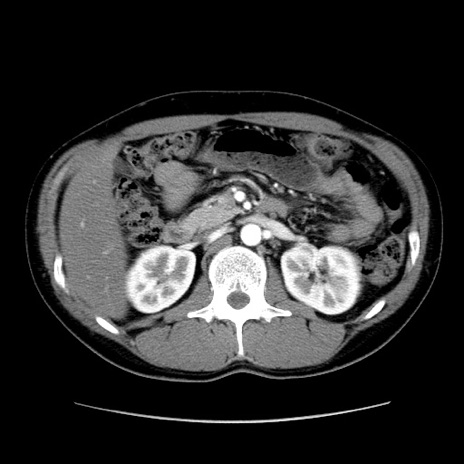

症例36(横断像)

【症例】20歳代 男性

【主訴】心窩部痛

【現病歴】今朝より上腹部痛あり。一旦軽快していたが再度出現したため救急要請。昨日夕に白身の魚を含む刺身を食べた。

【身体所見】BP 136/89mmHg、HR 74/min、BT 37.0℃、腹部:膨満、軟、心窩部に圧痛あり。反跳痛なし、筋性防御なし、腸雑音やや亢進あり。

【データ】WBC 17700、CRP 0.48